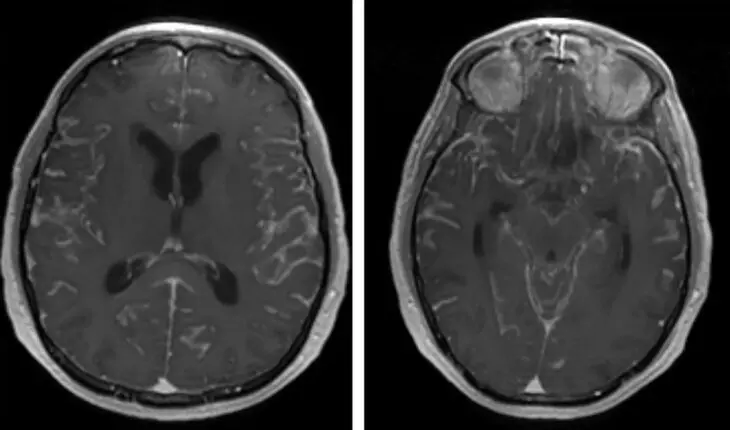

Photo by Filmbetrachter on Pixabay